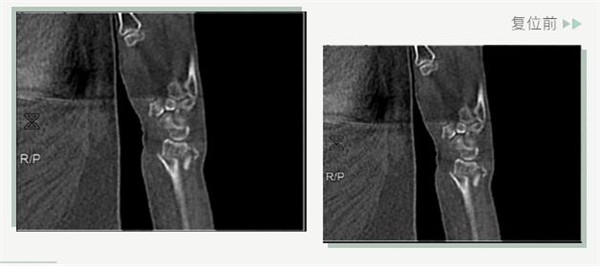

復(fù)位前

25日當(dāng)天,莊阿婆來(lái)到危立軍副院長(zhǎng)門診,經(jīng)拍片顯示,莊阿婆左橈骨遠(yuǎn)端粉碎性骨折,左髂骨至髖臼后緣及恥骨下支骨折??紤]到莊阿婆年紀(jì)較大,基礎(chǔ)病較多,難以經(jīng)受手術(shù)創(chuàng)傷,傳統(tǒng)手法復(fù)位更為合適。推、拽、按、捺……經(jīng)過(guò)危立軍副院長(zhǎng)一番手法復(fù)位后,再次拍片顯示莊阿婆橈骨遠(yuǎn)端骨折端復(fù)位位置良好,莊阿婆及其家人感到非常滿意。

復(fù)位后